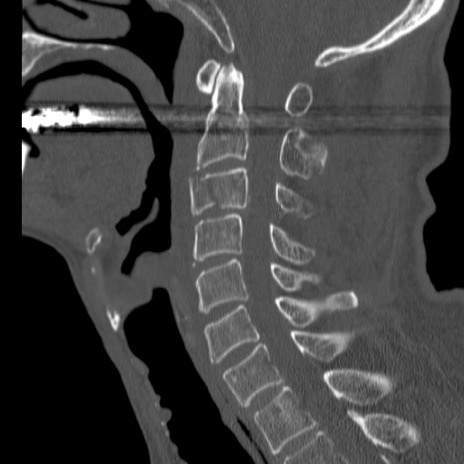

症例46 頚椎CT(矢状断像)

【症例】80歳代男性

【主訴】両側頚部〜上肢のしびれ

【現病歴】昨日、自宅内で転倒、その後より上記症状あり。意識障害なし。

【身体所見】両側上肢のallodynia(熱痛覚過敏)あり。MMTおよびDTRは正確な所見取れず。両上肢の挙上はなんとか可能。

異常所見と診断は?